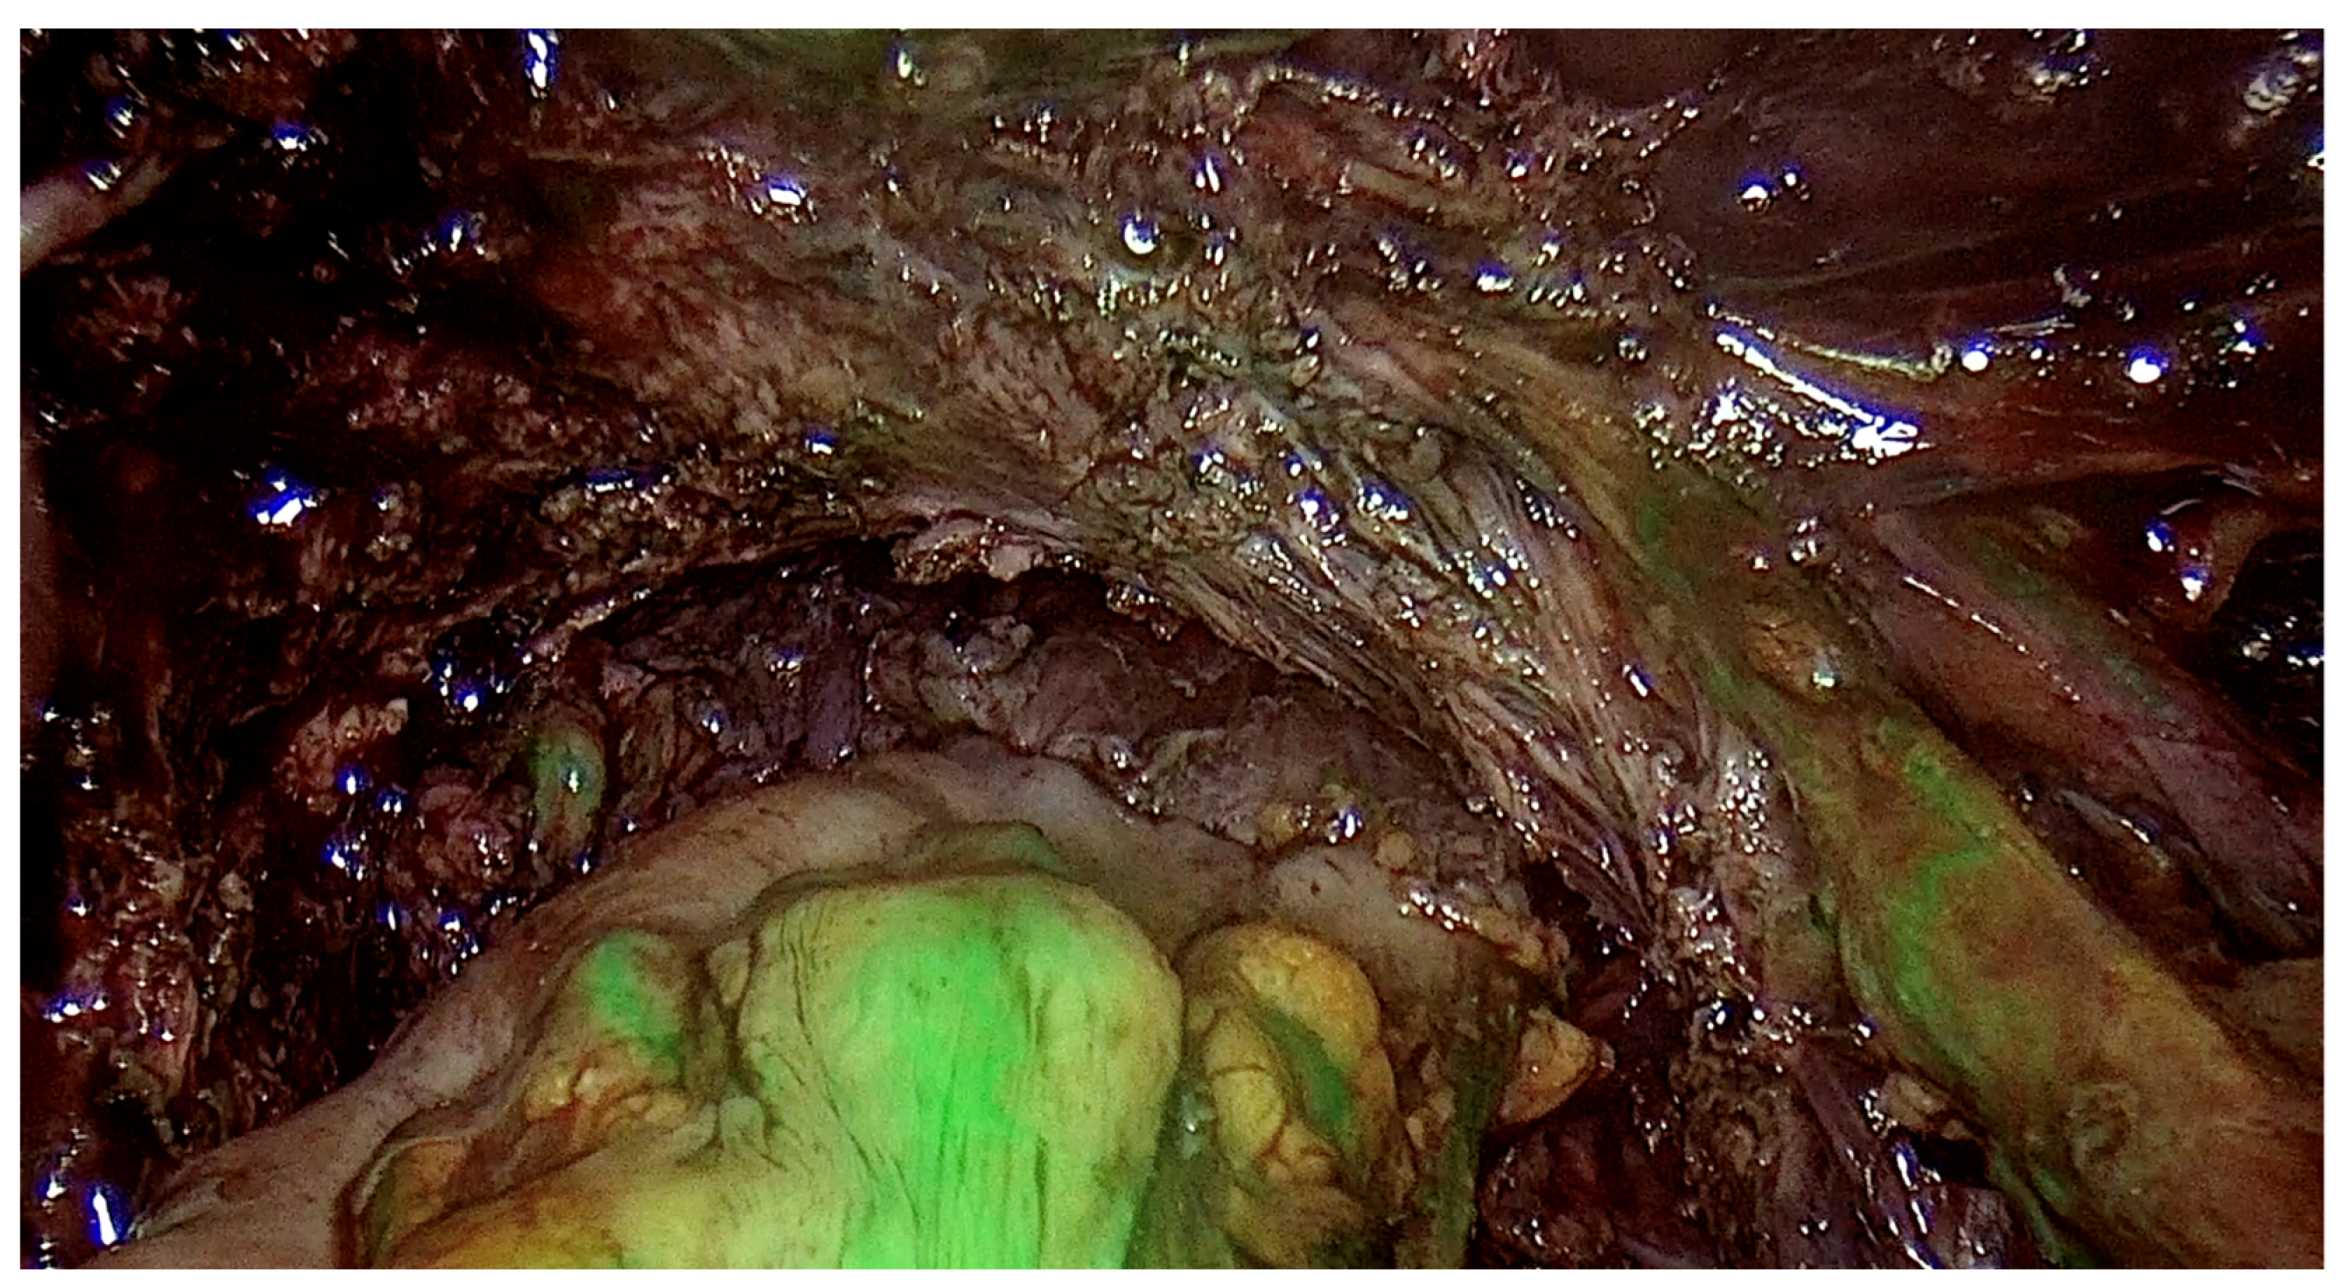

The range of the surgery was wide and consisted of modified radical hysterectomy, unilateral or bilateral infiltration of USLs and RVS resection, unilateral or bilateral ovarian cystectomy or drainage, large bowel resection procedures (shaving, discoid resection, segmental resection of the rectum, sigmoid colon, caecum), partial bladder resection, unilateral or bilateral ureterolysis sometimes with ureteral retransplantation, small intestine segmental resection, adnexectomy, nephrectomy, diaphragmatic lesions resection, bone, nerve and vessel lesion resection, and 2 cases of thoracic interventions. An image of the laparoscopic procedure with advanced bowel surgery is shown in Figure 3 and Figure 4.

Figure 3.

Intraoperative image of laparoscopic procedure—deep endometriosis affecting the bowel the nodule before the excision.

Figure 4.

Intraoperative image of laparoscopic procedure—the ICG testing of the bowel after the nodule excision.